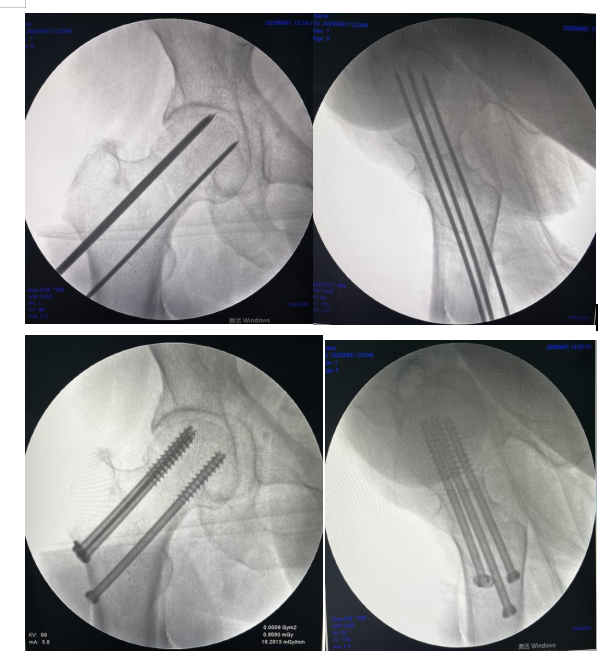

术中三臂机器人复位六轴机器人辅助经皮空心钉

术中术后透视